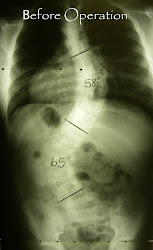

My name is Hanli and I have scoliosis and have been treated by Dr Koos Louw since I was 6 years old. I used to wear a brace, but since then my scoliosis had deteriorated. On 01 July 2010, I had scoliosis repair surgery at the Pretoria East Hospital. The operation lasted about 5 hours.